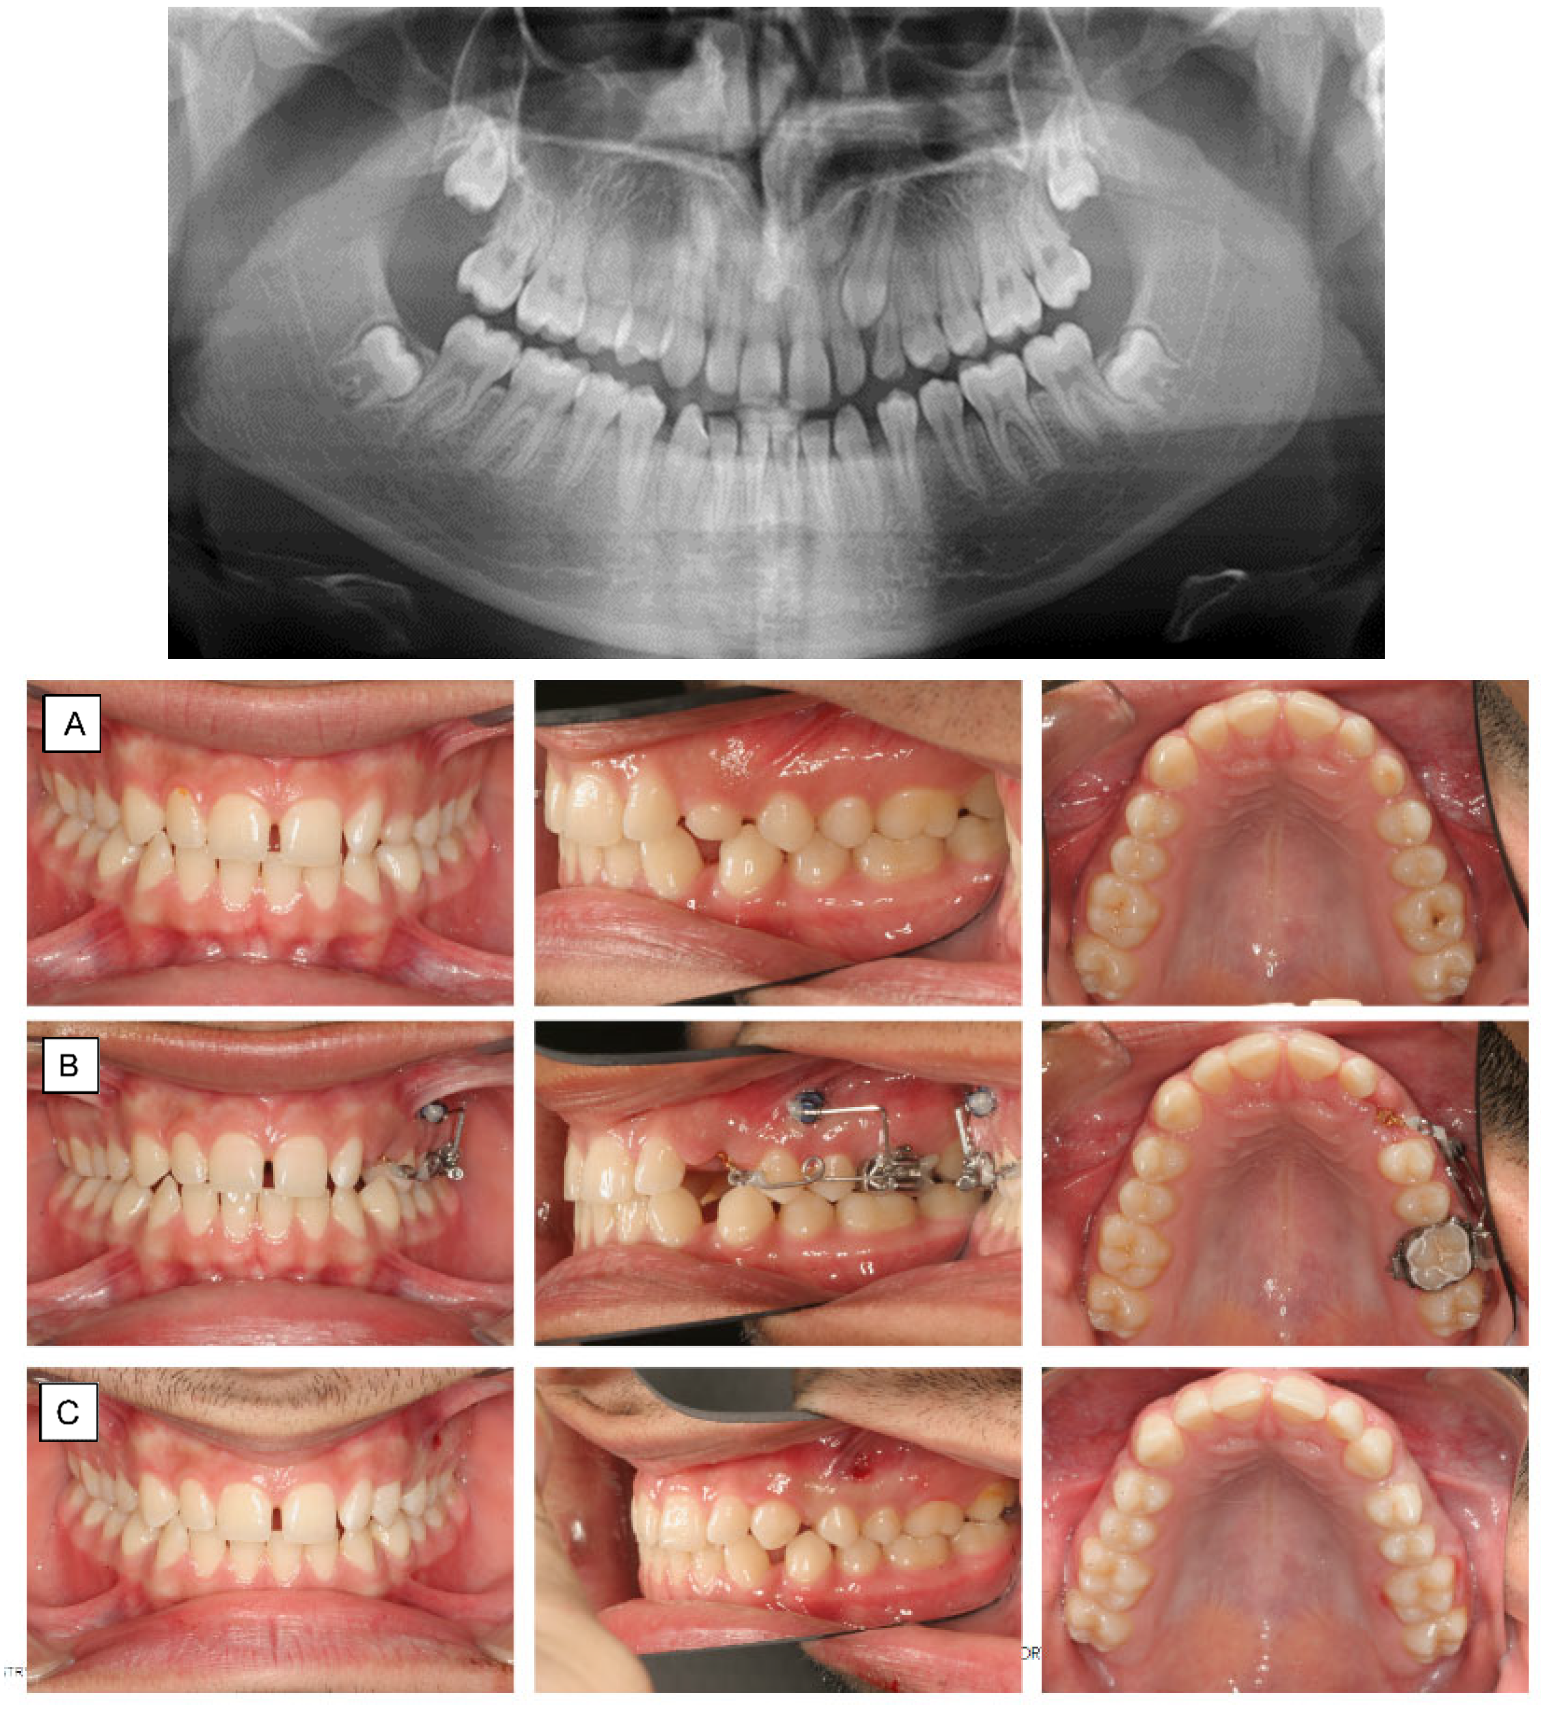

2. Anchorage Considerations

3. Impacted Teeth

3.1. Buccal Impaction

3.2. Palatal Impaction

10. Molar Uprighting